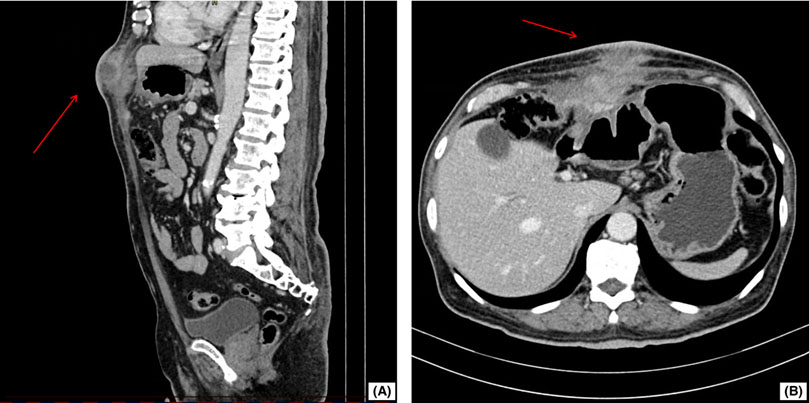

La tomografía computarizada (TC) abdominal (Figura 1) mostró un engrosamiento focal del colon transverso con una lesión inflamatoria mal definida que se extendía hacia la pared abdominal y una colección sugestiva de fístula colocutánea, estos hallazgos aumentaron la sospecha de un proceso neoplásico. La TC torácica contrastada no evidenció alteraciones. Los resultados de laboratorio relevantes se presentan en la Tabla 1.

Figura 1 Tomografía computarizada abdominal en vistas sagital y axial. (A) Vista sagital del abdomen: En la imagen se muestra una masa de tejido blando de densidad heterogénea, claramente delimitada (señalada con flecha roja), ubicada en la pared abdominal y que se extiende hacia la superficie cutánea. (B) Vista axial del abdomen: Se visualiza una masa de tejido blando (flecha roja) adherida a estructuras viscerales, compatible con la presencia de adherencias multiorgánicas.